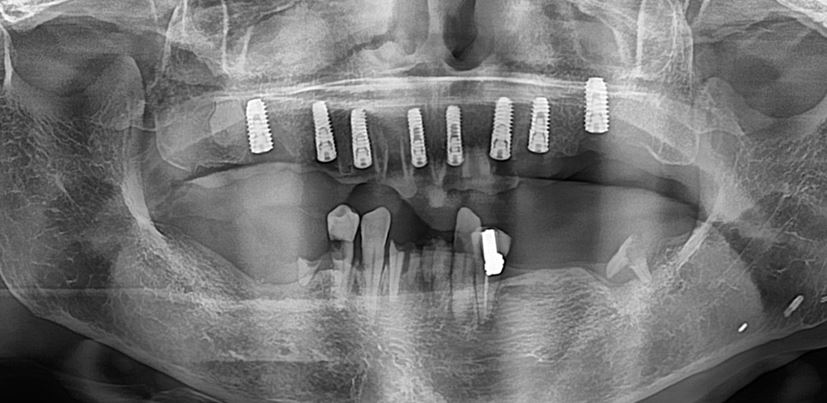

내원 당시 치아 상태

모든 치아가 썩어서 파절되고 교합이 없는 상태로 음식물 섭취가 전혀 되고 있지 않은 상태였습니다.

상악 전체 임플란트 식립

환자의 모든 상태를 고려하여 빠르고 안전한 임플란트 수술 진행

(수술 시간은 약 1시간 소요)